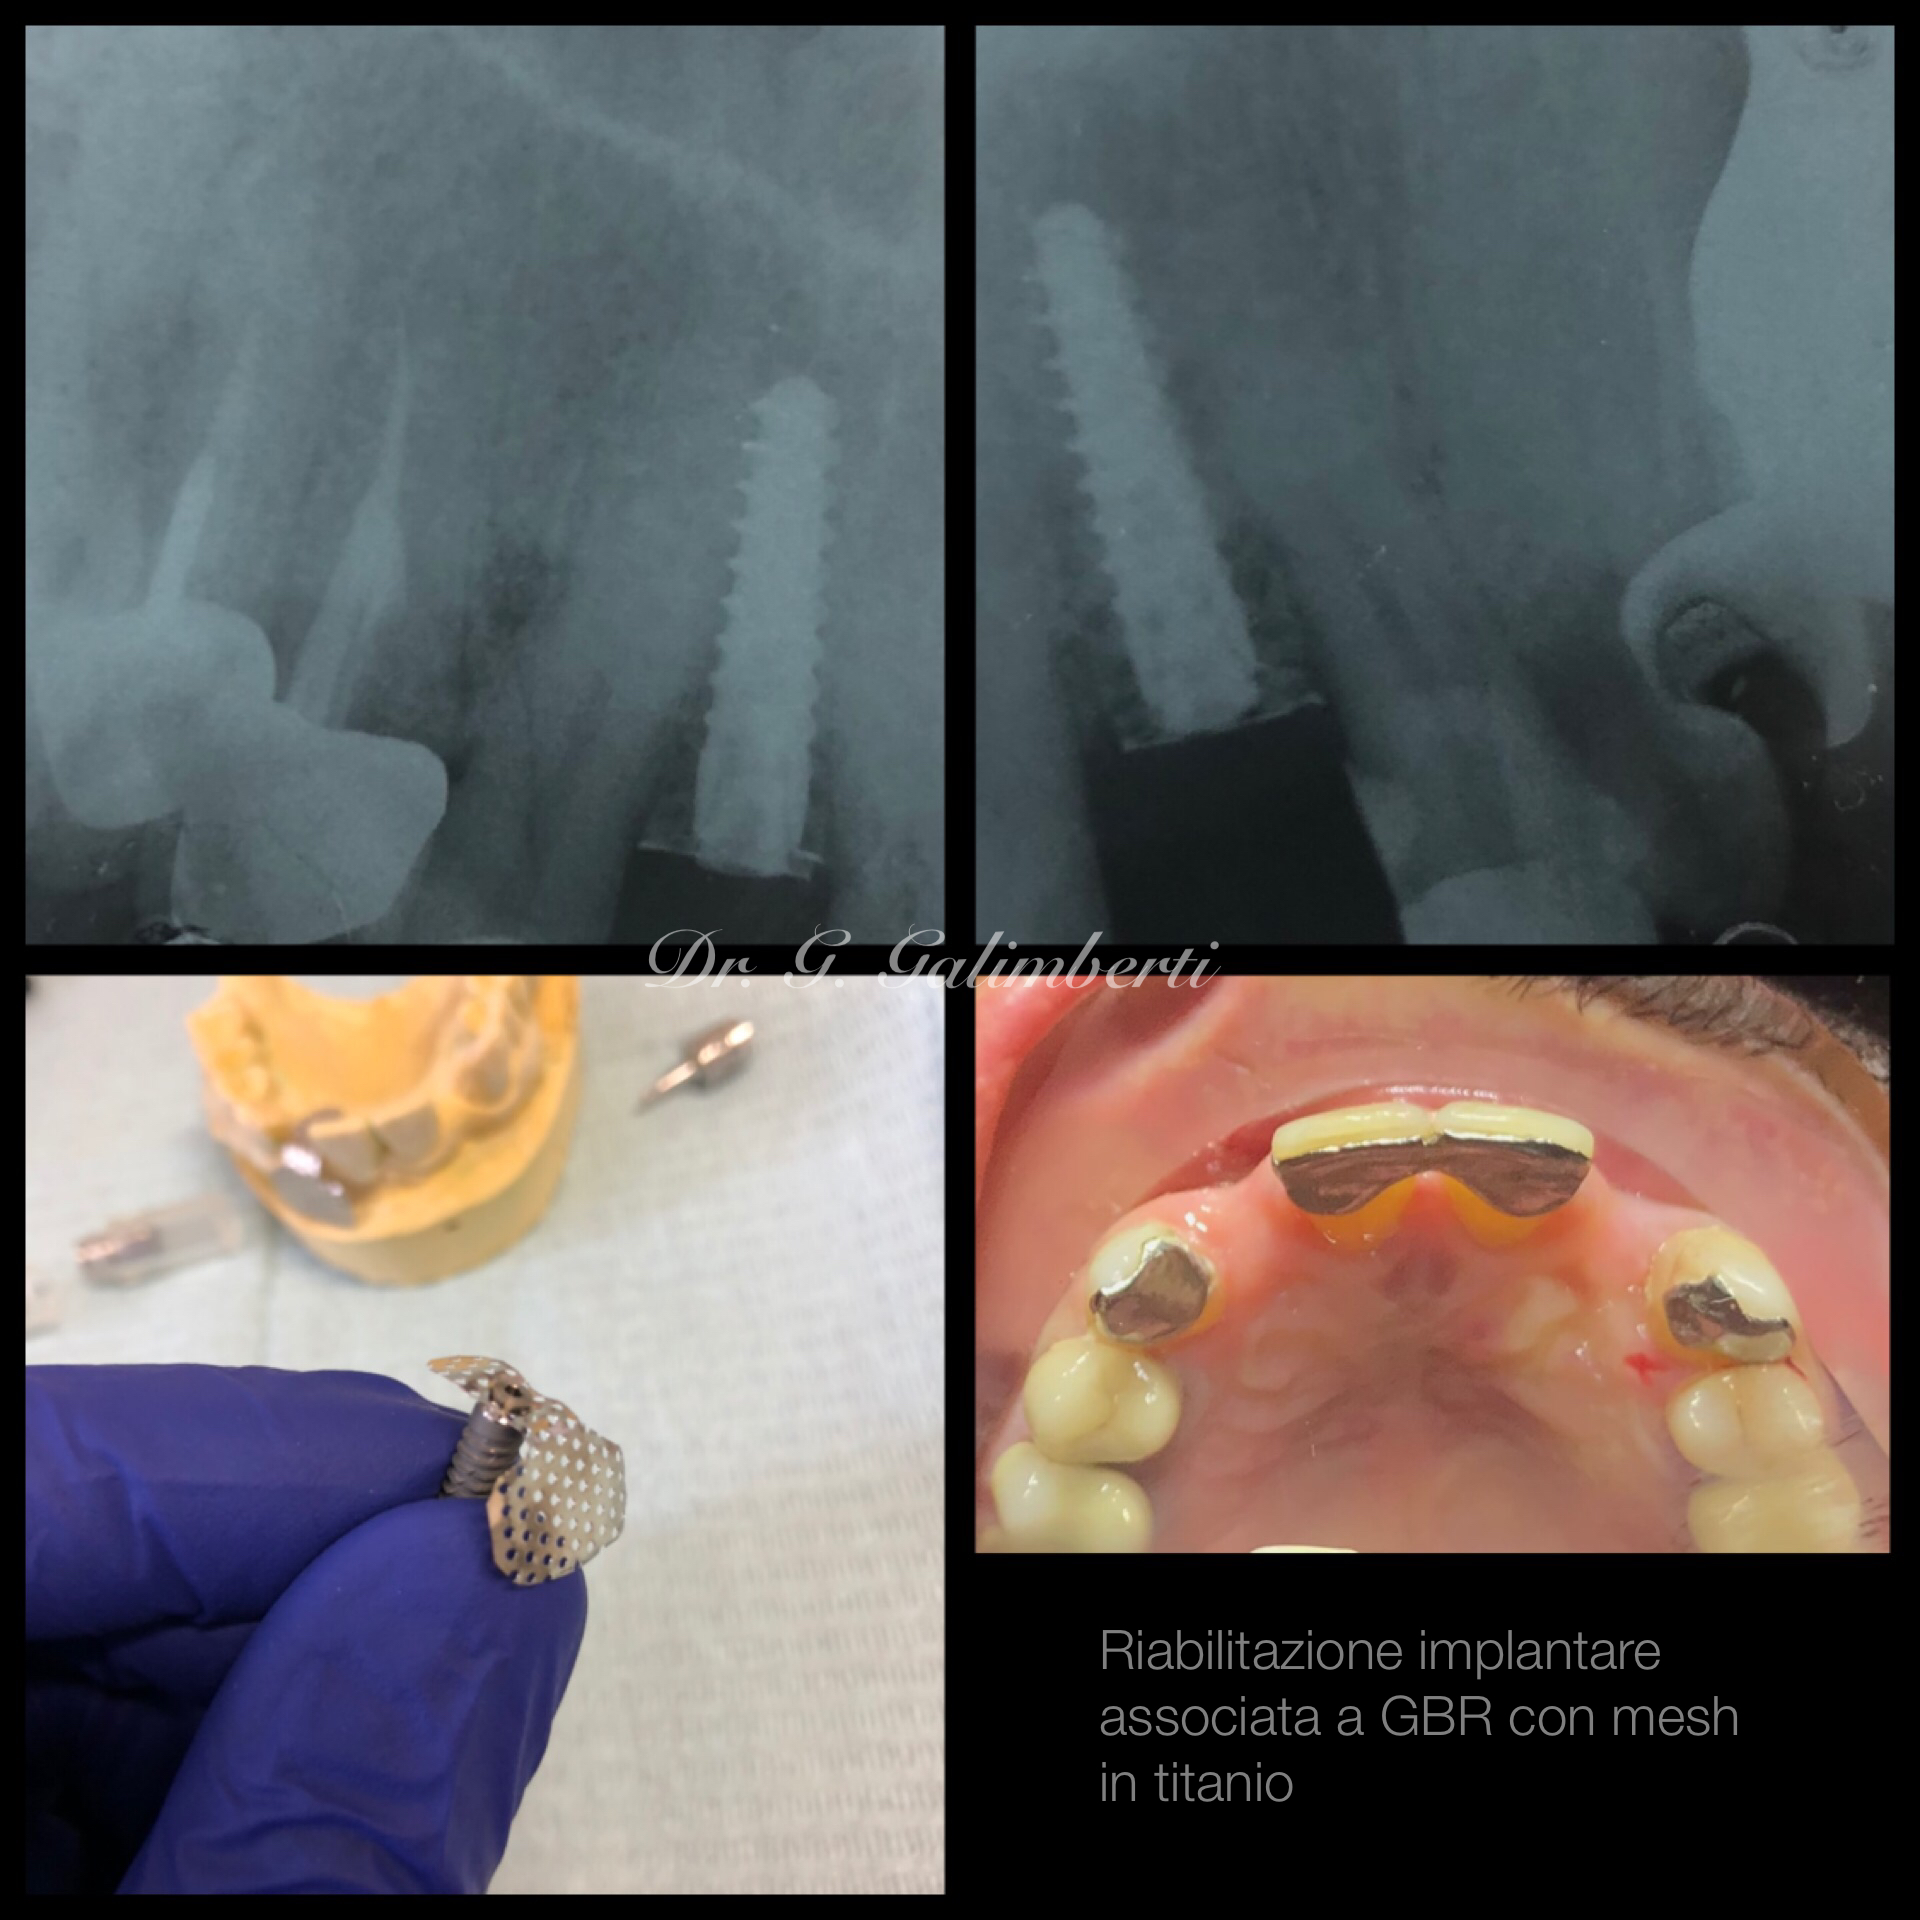

Con l’implantologia oggi è possibile sostituire un solo dente come un’intera arcata anche in casi di deficit ossei grazie alla GBR (rigenerazione ossea guidata) che ci permette di intervenire quando la disponibilità ossea iniziale del paziente non sarebbe sufficiente.